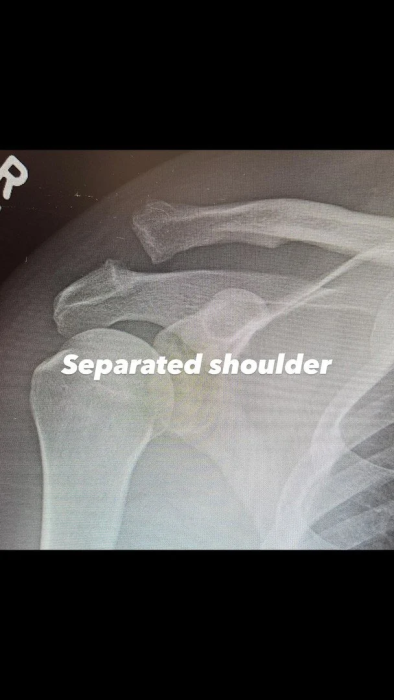

Плече Ченнінга Татума до операції. Фото: instagram.com/channingtatum

Актор також поділився рентгенівськими знімками плеча - до та після хірургічного втручання. Водночас він не став розкривати, за яких обставин отримав травму. Ченнінг лише зазначив, що попереду на нього чекає непростий період відновлення, але він налаштований упоратися з усіма труднощами.